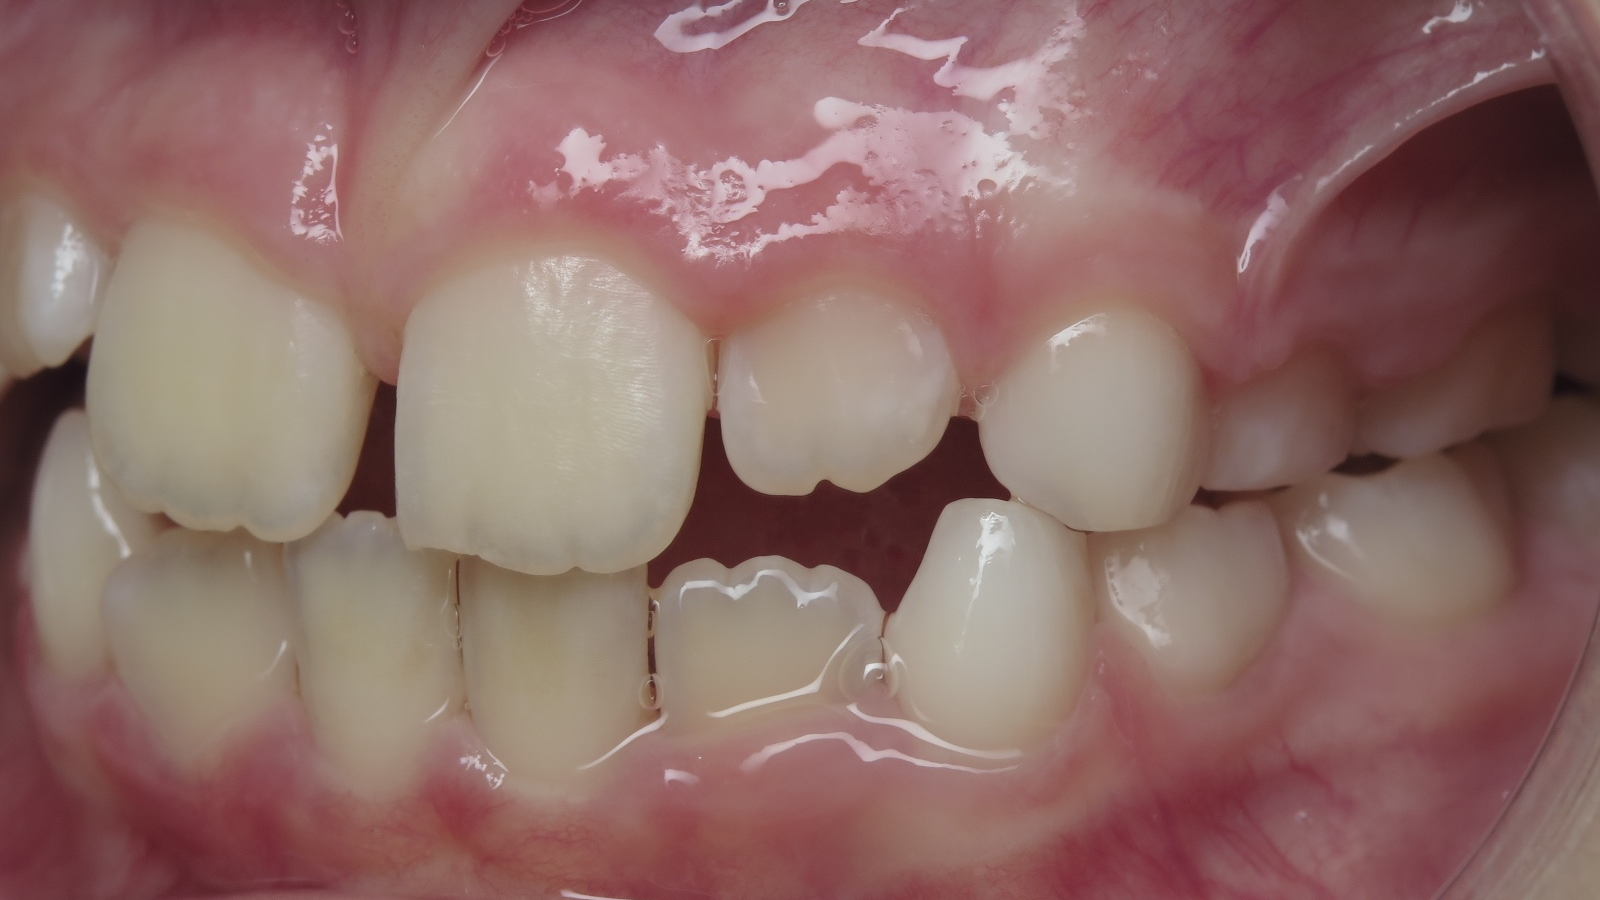

sectionnel multibagues pendant 8 mois

surveillance évolution de la dentition

bilan de début et en cours de traitement